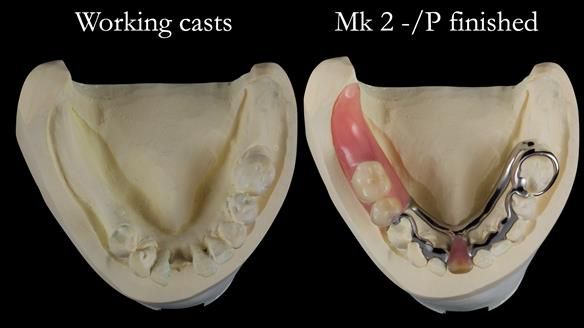

Welcome to my Newsletter 54 showing the making and fitting of dentures (a complete upper metal reinforced denture, a lower immediate partial denture and a definitive Scandinavian designed, metal based lower partial denture) for David, a 75 -year-old man. The full protocol workflow is presented including the use of dentate photographs to mimic his natural teeth.

The clinical situation and treatment process is shown in detail below. I provided the clinical work. Rowan Garstang, my dental technician, provided the technical work.

Interestingly we found that the upper complete denture when finished and fitted didn’t have good enough retention for David’s satisfaction. It was relined by adding compound to the buccal flanges – to almost overextend into the sulcus to ‘create’ a sulcus, followed by using a light bodied silicone impression material. This improved the function of the C/-considerably. A lower Scandinavian hygienically designed lower RPD was also provided which helped with occlusal stability and reseating the upper denture – further improving the fit.